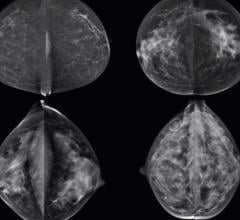

Nancy Cappello, Ph.D., executive director and founder of Are You Dense Inc. and Are You Dense Advocacy, explains how a ...

While most women understand the importance of health screenings, an estimated 72 million have missed or postponed a ...